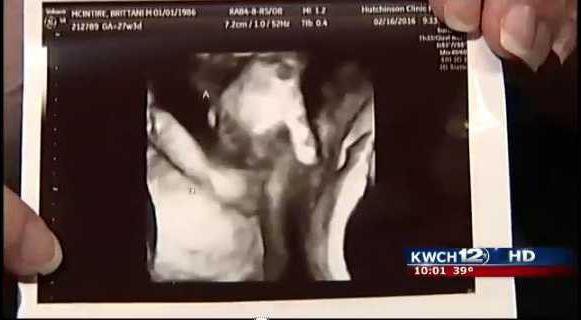

Dying twin holds his sisters hand in special sonogram

A pregnant mother carrying twins was told one of her unborn children wouldnt make it, but she was comforted by what she saw in her sonogram. - photo by Nick Anderson

In a story from KWCH News in Kansas, Brittani McIntire and her husband Ian went to the hospital for the six-week sonogram where the doctors told them they would be having twins one boy and one girl. Unfortunately, the boy had a hole in his heart and an abnormal brain. He weighed significantly less than his sister.

But then an image captured by another sonogram showed something unexpected.

"We didn't really see much, Brittani said to KWCH. She said there's his hand and there's her hand and it looks like they're holding hands.

The sonogram showed the boys hand holding onto his sisters finger.